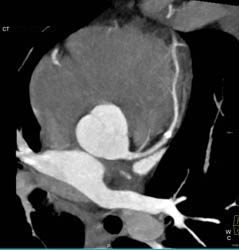

Diagnosis

Diseased LAD